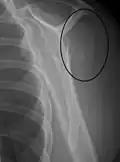

Multi-fragmented, or comminuted fracture of the proximal humerus with involvement of the greater tuberosity -

Proximal humerus fracture -